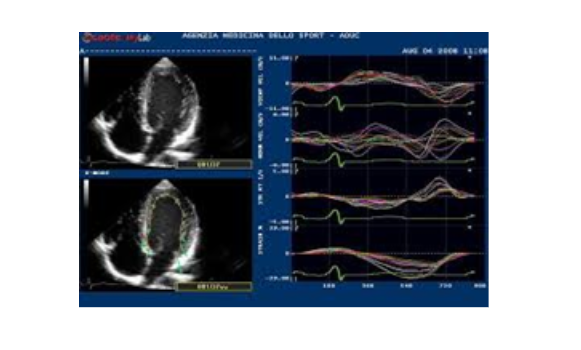

Các kiểu siêu âm tim

Khi chùm tia siêu âm đi qua 1 vật thể chuyển động sẽ sinh ra hiệu ứng Doppler. Hiệu ứng Doppler là đại lượng phản ánh vận tốc của vật thể chuyển động được thu nhận, xử lý và biểu hiện qua dạng âm thanh, dạng sóng hoặc mã hóa thành màu. Trong siêu âm Doppler tim, hiệu ứng Doppler phản ánh vận tốc chuyển động của dòng máu và của cơ tim. Dòng máu đi qua chỗ hẹp có vận tốc lớn, khi đó tín hiệu âm thanh sẽ có âm lượng lớn và âm sắc cao, tín hiệu dạng sóng sẽ có biên độ lớn. Với Doppler mầu, dòng máu được mã hóa thành mầu đỏ nếu đi về phía đầu dò và thành mầu xanh khi đi xa đầu dò, theo đó sẽ phát hiện được các dòng máu bất thường trong tim. Nói một cách ngắn gọn, siêu âm Doppler tim là phương tiện rất hữu hiệu trong đánh giá huyết động qua các van tim, phát hiện các dòng máu bất thường trong tim và tình trạng vận động của cơ tim.